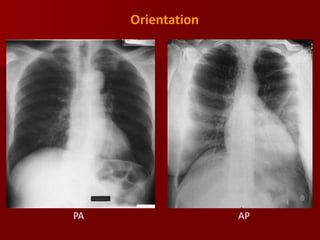

Orientation:

In this we are making reference to the position of the patient

and the x ray beam.

A PA radiograph is obtained with the x-ray traversing the

patient from posterior to anterior and striking the film.

Similarly an AP radiograph is positioned with the xray

traversing the patient from anterior to posterior striking the

film.

 The cardiac border will appear larger on an AP radiograph

due to the magnification effect of the more anteriorly located

heart relative to the film.

Difference between P.A & A.P VIEW

In PA view

 Clavicles don’t project too high into the apices or

thrown above the apices (more horizontal)

 Heart wont be magnified over the mediastinum

therefore preventing the appearance of

cardiomegaly

 Scapula are away from the lung fields

 Ribs are obliquely oriented in PA view

 Spine and posterior ends of ribs are clearly seen

Orientation

PA

AP